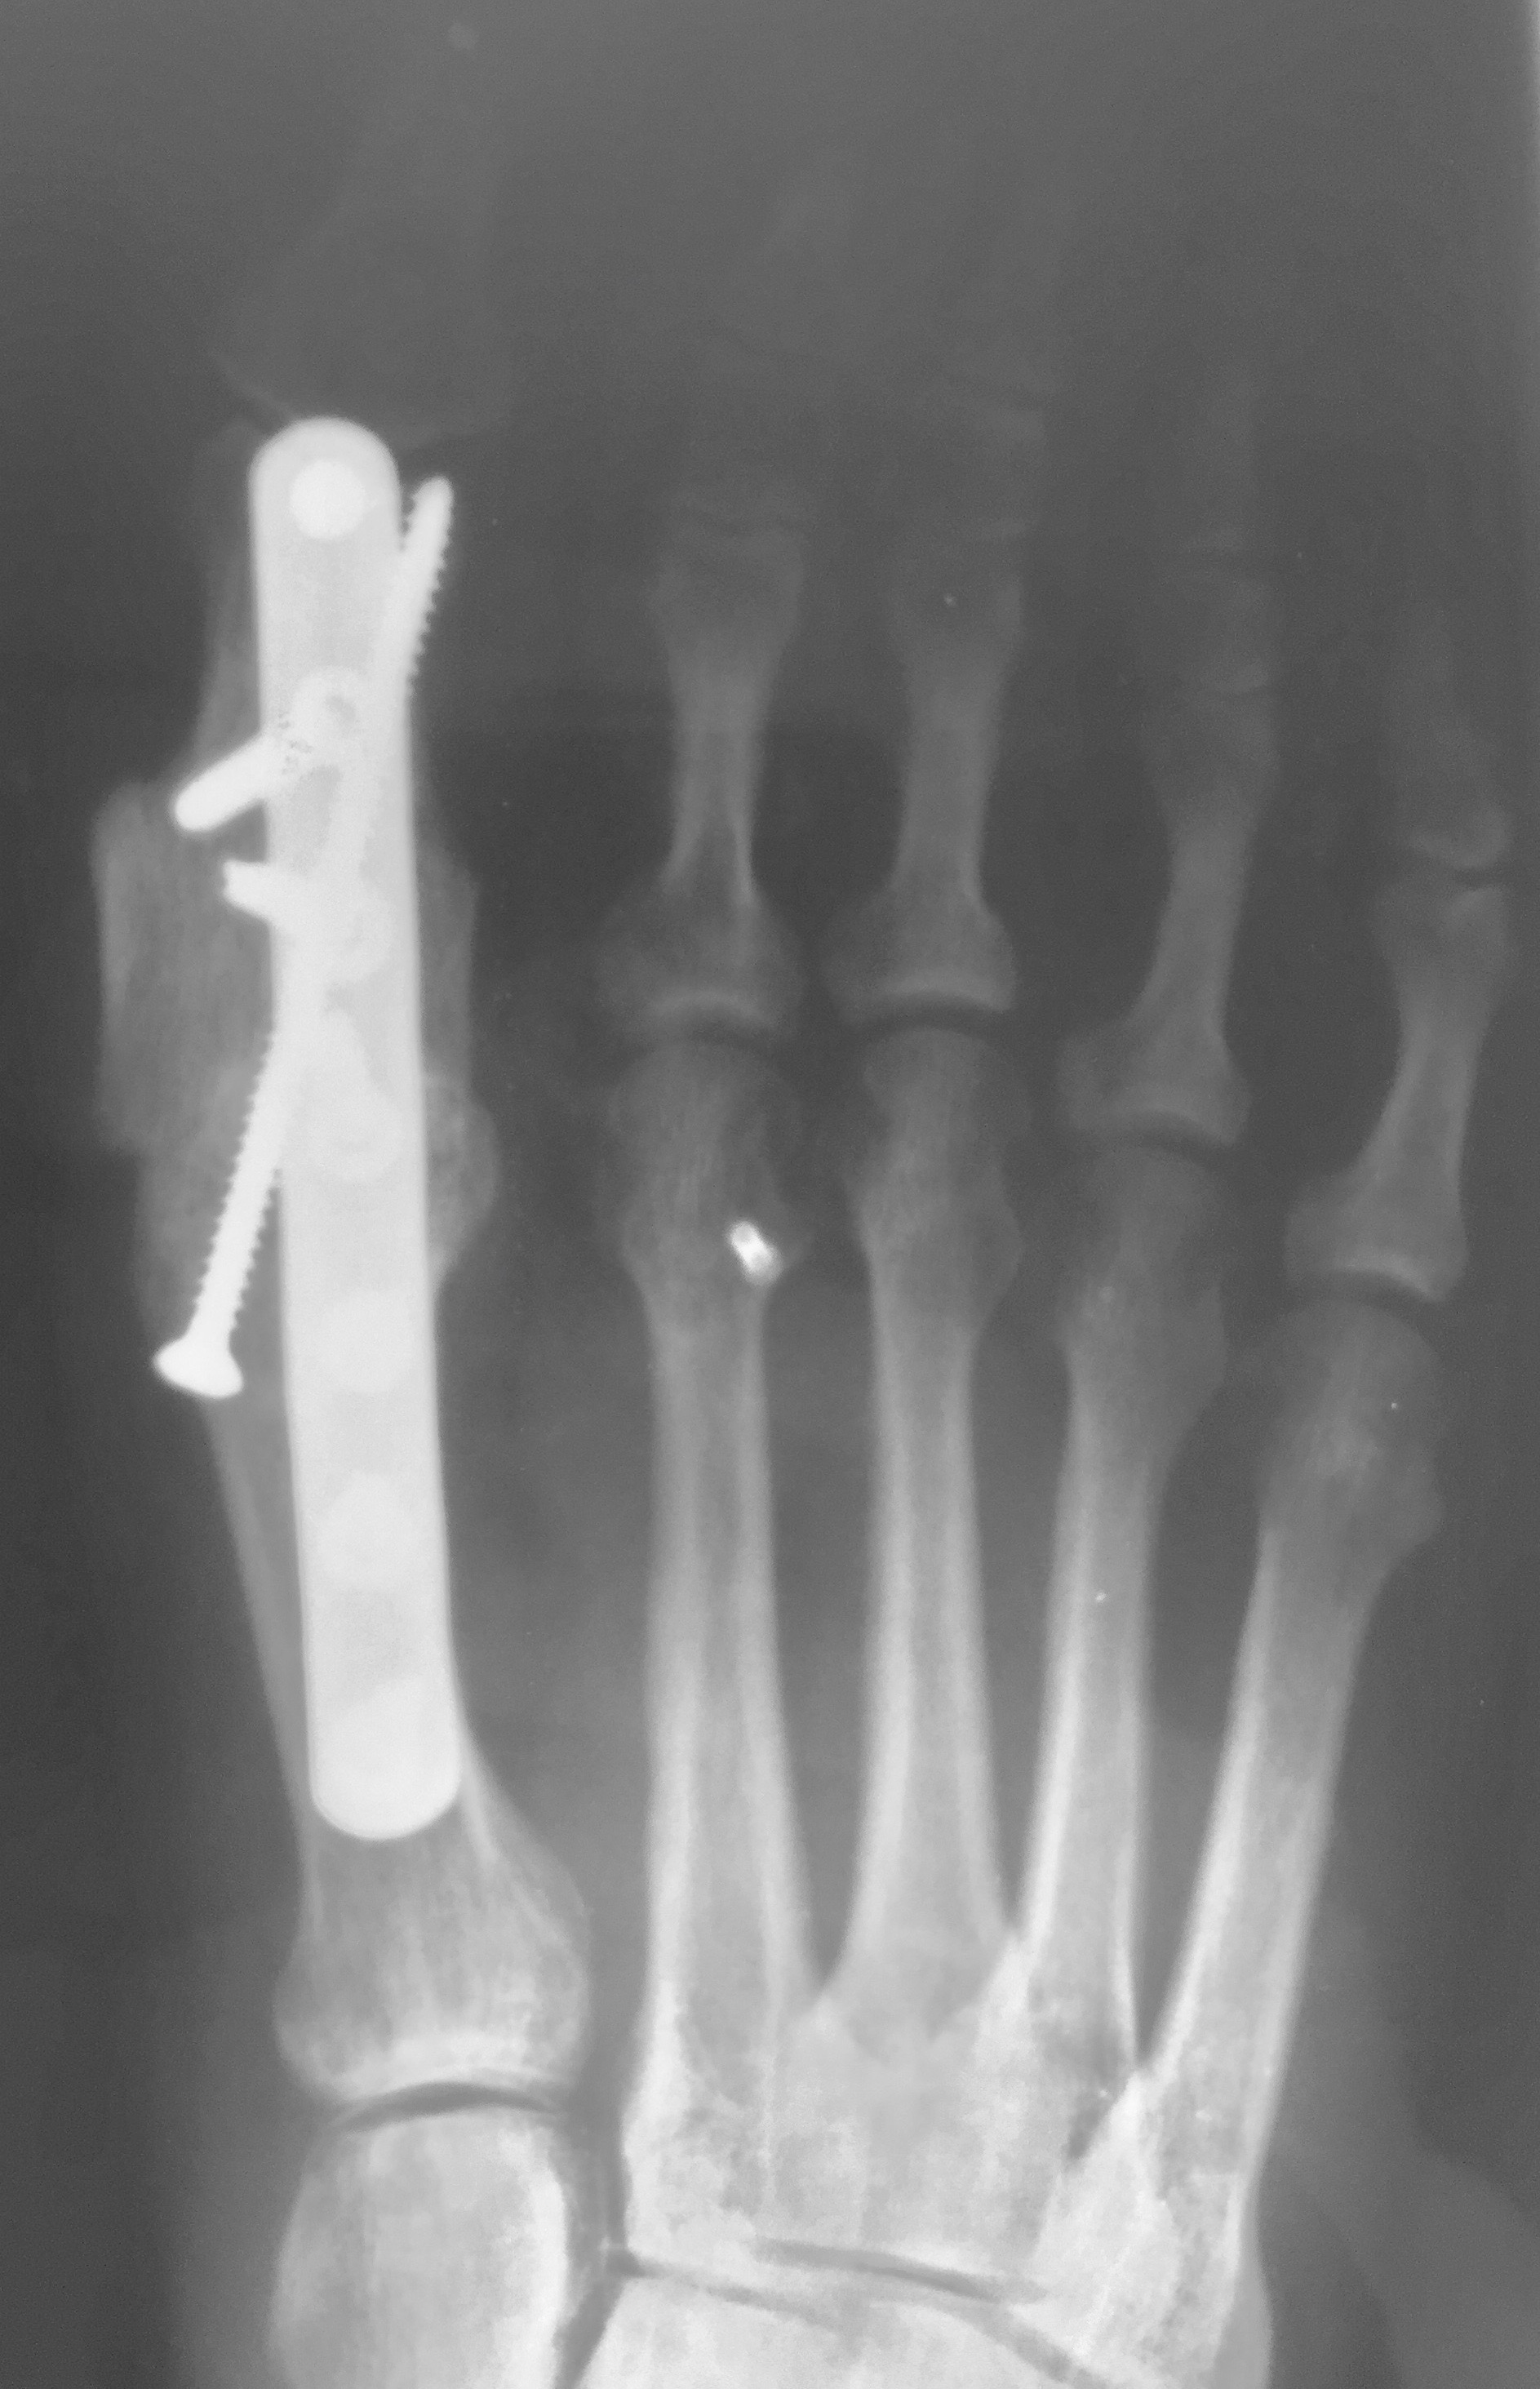

Great Toe Joint Fusion Surgery Alexandria VA Podiatrist Foot Bone Graft Bone graft material in common foot and ankle procedures. A bone graft is a surgical procedure used to fix problems with bones or joints. There are many methods, including. A bone graft is a choice for repairing bones almost anywhere in your body. A doctor may recommend a bone graft for many conditions, including fractures, infections, and spinal fusion. Your. Foot Bone Graft.

1st MTPJ Fusion Big Toe Arthrodesis David Redfern Foot Bone Graft A bone graft is a procedure to apply bone tissue or similar substances to damaged bones. A doctor may recommend a bone graft for many conditions, including fractures, infections, and spinal fusion. Almost 1 million bone grafting procedures performed in us each year, with a growth of almost 13% per year. There are many methods, including. Your surgeon might take. Foot Bone Graft.